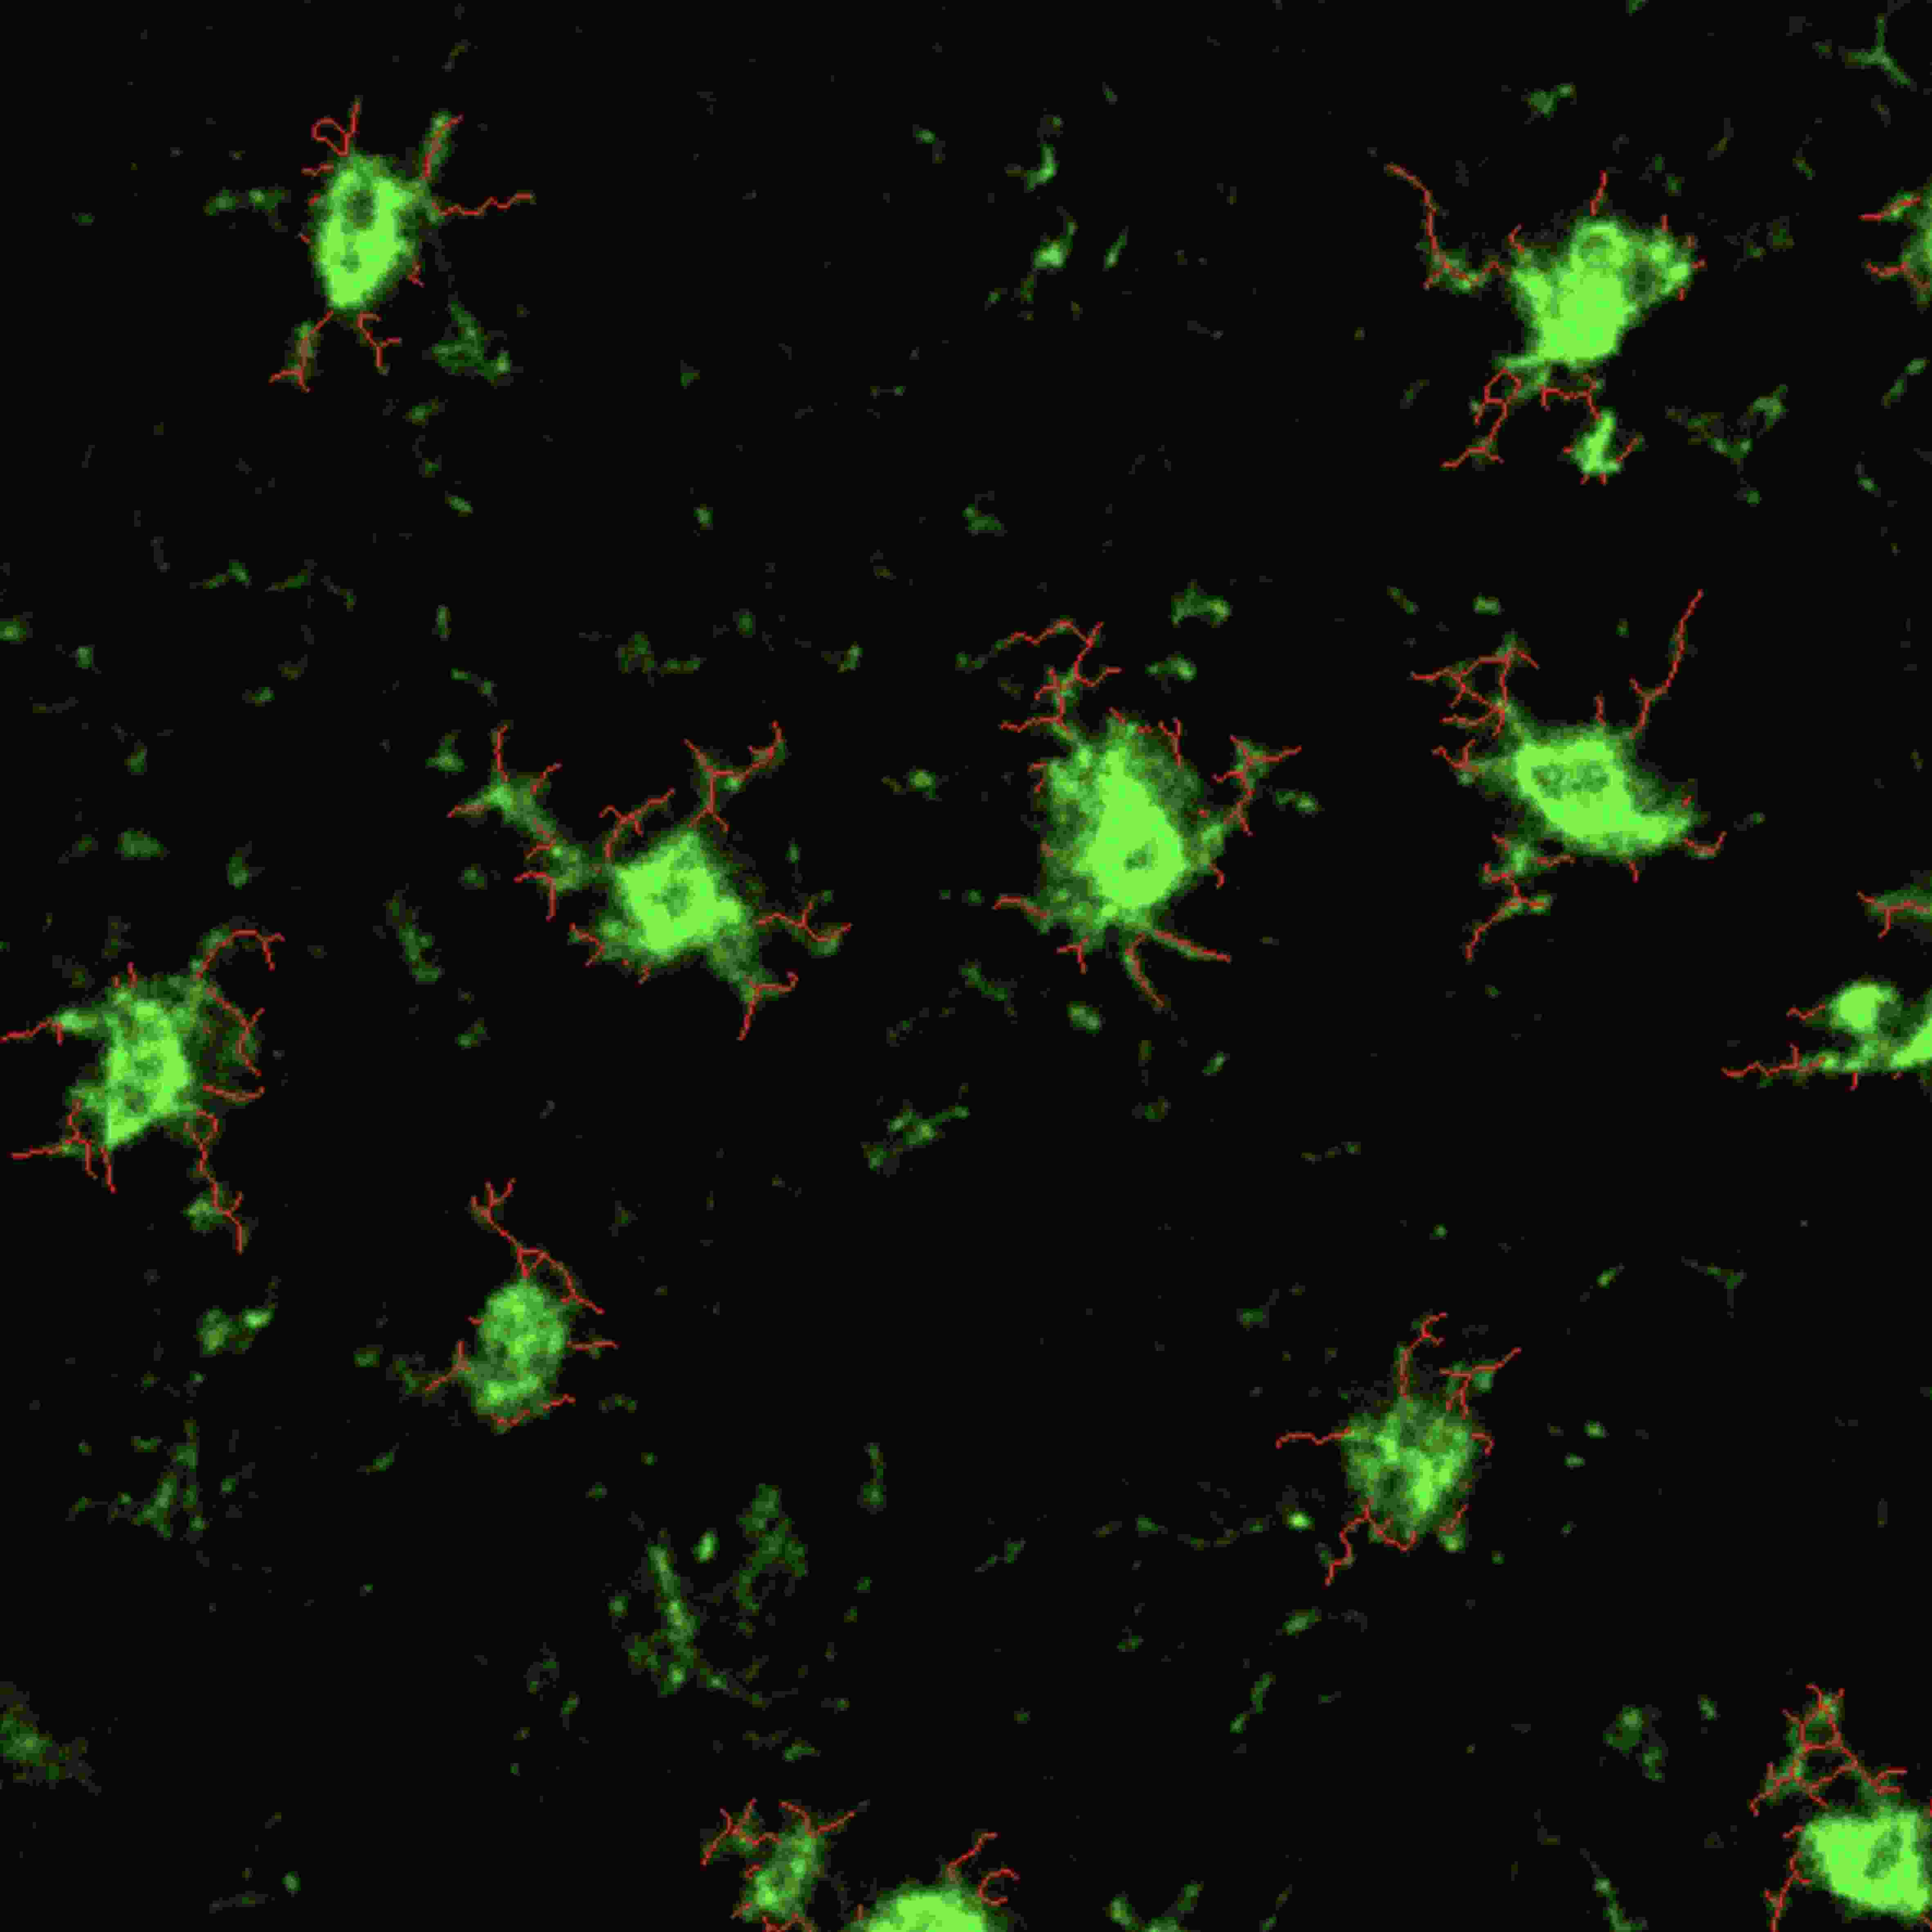

通过高分辨率的显微镜技术,研究人员可以在细胞核分子水平上观察神经细胞的结构变化、蛋白质表达和信号传递过程。

分析内容:胞体个数、胞体平均面积、胞体染色强度、和胞体连接的神经纤维个数及长度